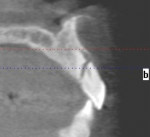

Following the technique for immediate extraction, immediate implant placement and provisionalization procedures outlined previously, the patient had teeth Nos. 7 through 9 removed by atraumatic, minimally invasive means, debridement was accomplished, and 3 implants were placed: a NobelActive implant (Nobel Biocare, nobelbiocare.com) measuring 3.5 mm x 11.5 mm at No. 7; and 2 NobelActive implants measuring 3.5 mm x 13.5 mm placed at Nos. 8 and 9 respectively, with each implant obtaining an ISQ of 50 Ncm at placement. Implant placement was accomplished by a minimally invasive (flapless) protocol. Reconstruction of the missing buccal plate in the region of teeth Nos. 7 through 9 was accomplished once again by an allogenic, mineralized, cancellous 1-mm to 2-mm-particle-size bone graft (LifeNet Health, lifenethealth.org) condensed into the peri-implant defects, to the level of the crest of the bone-level NobelActive implant (Figure 16). Provisional QuickTemp Abutment Conical Connection (Nobel Biocare) were screwed into place, and an immediate provisional restoration constructed from the retrofitted TempStent II surgical guide32 provisionalization system. The provisional restoration was cemented with Temp-Bond™ Clear (Kerr, kerrdental.com), and the excess cement was removed. The patient was allowed to follow a 3-month healing and observation period after which fixture-level impressions were obtained and computer-aided design and computer-aided manufacturing custom-milled zirconia abutments were constructed. This was followed by a second set of provisional restorations the patient utilized for an additional 2 months. Final impressions were taken of the zirconia abutments, and final all-ceramic restorations were constructed and cemented into place. The case’s complete clinical view can be seen in Figure 17. Figure 18 shows the 4.5-year post-treatment clinical view, while Figure 19 shows the 4.5-year post treatment computed tomography (CT) scan serial view. Please note that the total reconstruction of the buccal bone structures achieved by the minimally invasive bone graft procedure was accomplished following the technique previously outlined.

A 49-year-old nonsmoking male presented for treatment of his advanced tooth loss, terminal dentition, residual infection after dental treatment, and recurrent sinus infections. His dental history consisted of multiple attempts at conventional treatment approaches to prolong tooth longevity, several implant procedures to replace failing endodontically treated teeth and edentulous sites (all resulting in repeated failure of treatment), compromised esthetics, and various secondary infectious diseases related to previous failures of dental treatment. The pretreatment CT scan view of the maxillae and several serial views (Figure 20) demonstrated multiple edentulous sites, residual sinus infections, failing implant procedures with large alveolar defects, and the remaining dentition, which can be classified as a “terminal dentition.” After reviewing multiple treatment options with the patient ranging from conventional fixed and removable options, to partial implant reconstruction with extensive bone replacement procedures recommended, the patient opted for removal of most of the remaining dentition, correction of sinus pathology, multiple implant placement, and immediate provisionalization procedures, most accomplished by a conservative, minimally invasive protocol (except for the sinus regions, which required flap access and a lateral-wall osteotomy), and immediate loading of the implants at the initial and only surgical procedure planned. After extensive medical and dental histories were taken, medical clearance for the preexisting sinus infections was obtained, and a complete dental workup consisting of a facebow transfer, mounted maxillary and mandibular pretreatment models, a complete diagnostic waxup of both the hard and soft tissues required to be replaced, and construction of the TempStent II surgical guide and provisionalization system, the patient was given an appointment for the complex surgical visit. During this surgery, remaining dentition and implants were removed, ten implants in the maxillary arch were inserted, and bilateral sinus elevations and alveolar reconstruction was performed along with peri-implant bone grafting and immediate provisionalization. In the mandibular arch, removal of the remaining dentition was done, except for teeth Nos. 21, 22, 27, and 28, and six implants were placed and immediately provisionalized, keeping the patient in the planned first-molar occlusion scheme. The immediate post-treatment panoramic view can be seen in Figure 21. After an uneventful healing for 4.5 months, the patient then initiated the final reconstructive phase of his treatment. A 7-year post-treatment clinical view can be seen in Figure 22, with the 7-year post-treatment CT panoramic scan, axial and serial views of the maxillary central incisor seen in Figure 23.